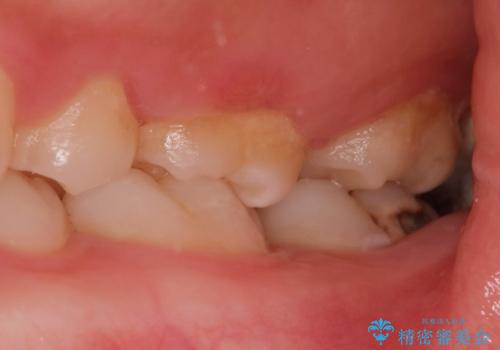

- 左下奥歯が痛いとの事で来院。

親知らずが炎症を起こしていたので抜歯をし、手前の歯は拡大鏡下で虫歯を取り除き、ジルコニアクラウンで治療をしました。

親知らずは歯ブラシがしにくく、虫歯のリスクが高いです。

手前の歯が虫歯になる前に抜歯をする事をお勧めします。